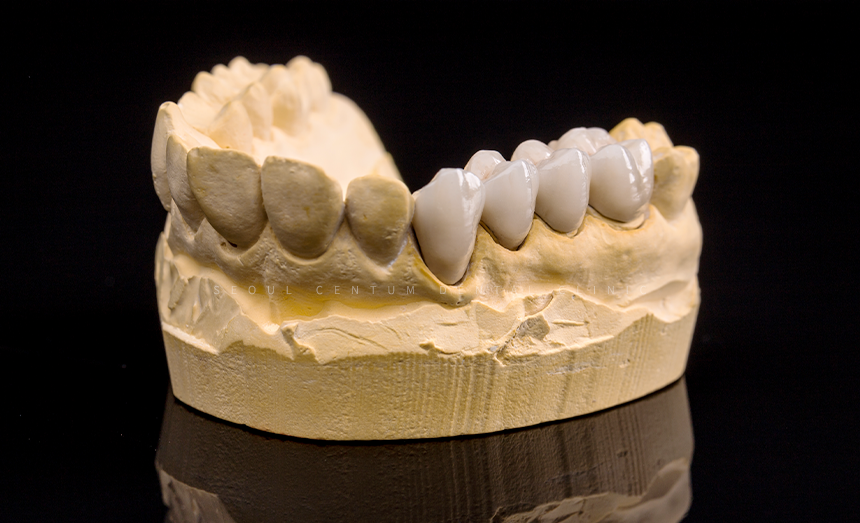

2주 후 기공소에서 받은

맞춤 크라운을 수복해 드렸으며

스크류도 단단히 조여서

풀리지 않게 고정해 드렸습니다.

교합과 인상 채득을 한 다음 크라운 제작을 위해

색상 대조 후 기공소에 의뢰했습니다.